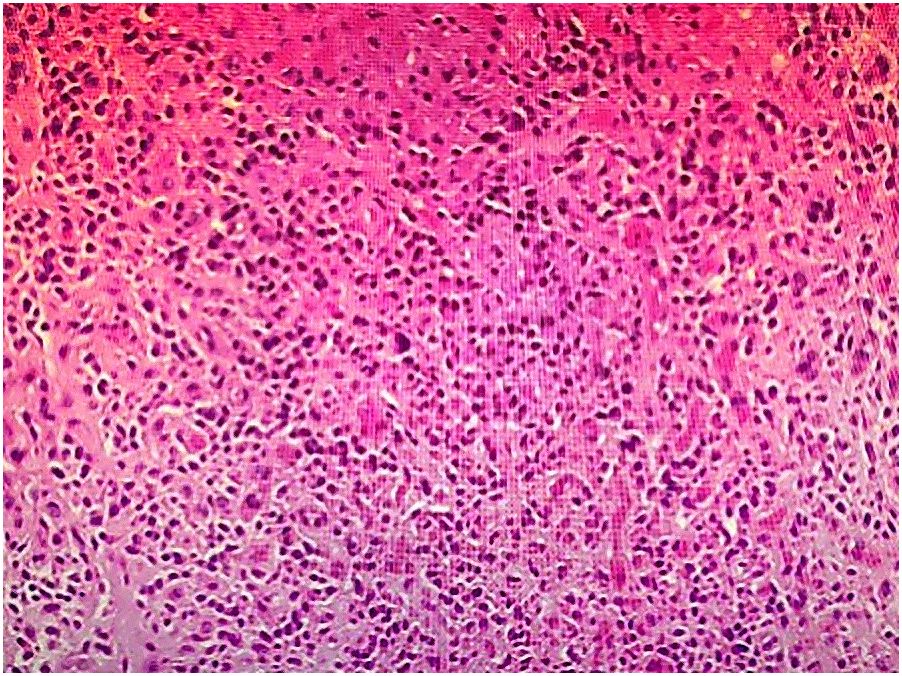

The patient underwent four cycles of neoadjuvant chemotherapy with etoposide (100 mg/m² on days 1–3) and carboplatin (AUC 5 on day 1), administered every 21 days. Follow-up CT imaging demonstrated substantial tumor regression, with a residual lesion measuring 0.7 × 0.6 cm and normalization of ureteral caliber (Figure 4).

Figure 4

CT scan of the abdominal region showing cross-sectional view of organs and tissues. The scan highlights distinct shapes and densities, including areas of lighter and darker shades representing different structures.

Figure 4. Follow-up CT after neoadjuvant chemotherapy demonstrating marked tumor regression (residual lesion: 0.7 × 0.6 cm) and normalization of ureteral caliber.